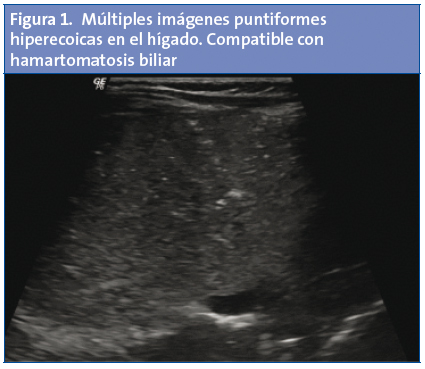

● Hamartomatosis ● HígadoLactante de un mes y medio de vida, alimentada con leche materna a demanda, derivada a las consultas externas de Gastroenterología de nuestro hospital por regurgitaciones frecuentes, cambio en el hábito intestinal (emisión de diez deposiciones diarias blandas, con moco), rectorragia intermitente y prolapso rectal. El estudio preliminar, que incluyó detección en heces de virus y bacterias, así como hemograma, bioquímica y estudio de coagulación, fue normal. Tres días antes de ser vista en las consultas externas, por progresión del número de vómitos, se le pidió desde Urgencias una ecografía abdominal, en la que se descartó la existencia de signos de estenosis hipertrófica de píloro; páncreas, bazo, riñones y vejiga fueron normales. El hígado mostró un tamaño normal y un borde liso, pero en él se identificaron múltiples imágenes puntiformes hiperecóicas (Fig. 1), alguna de ellas con artefacto en cola de cometa (Fig. 2), en relación con hamartomatosis biliar.

Los hamartomas de la HBM tienen un color blanco-grisáceo, y pueden estar localizados en la región subcapsular o dispersos por el parénquima. Su tamaño suele ser inferior a 3 mm, si bien en ocasiones pueden agruparse y alcanzar una longitud de 15 mm de diámetro3.

El diagnóstico de la HBM requiere inicialmente una prueba de imagen (ecografía, tomografía computarizada [TC] o resonancia magnética [RM])1-6. En la ecografía, la presencia de hamartomas múltiples hace que el hígado muestre un aspecto granular, heterogéneo, en el que destaca la presencia de numerosas áreas redondeadas hipoanecoicas con zonas hipercogénicas, artefacto en “cola de cometa” y refuerzo posterior. Con el eco-Doppler (Fig. 3) se puede visualizar un artefacto “de centelleo” (alternancia de color inmediatamente detrás de un objeto ecogénico estacionario), debido a las reverberaciones producidas por los cristales de colesterol que rellenan en ocasiones los conductos dilatados1-7. En la TC se aprecia la presencia de múltiples nódulos hipodensos8. Se ha postulado, especialmente en pacientes adultos, que la técnica de elección es la RM. Esta técnica aporta mayor sensibilidad y especificidad a la hora de hacer el diagnóstico diferencial con otros cuadros (Tabla 2). En la secuencia T1, los hamartomas se muestran como estructuras nodulares hipointensas con respecto al parénquima adyacente. En la secuencia T2 se ven como estructuras hiperintensas. Típicamente, los hamartomas no se comunican con la vía biliar, al contrario de lo que ocurre en la enfermedad de Caroli.